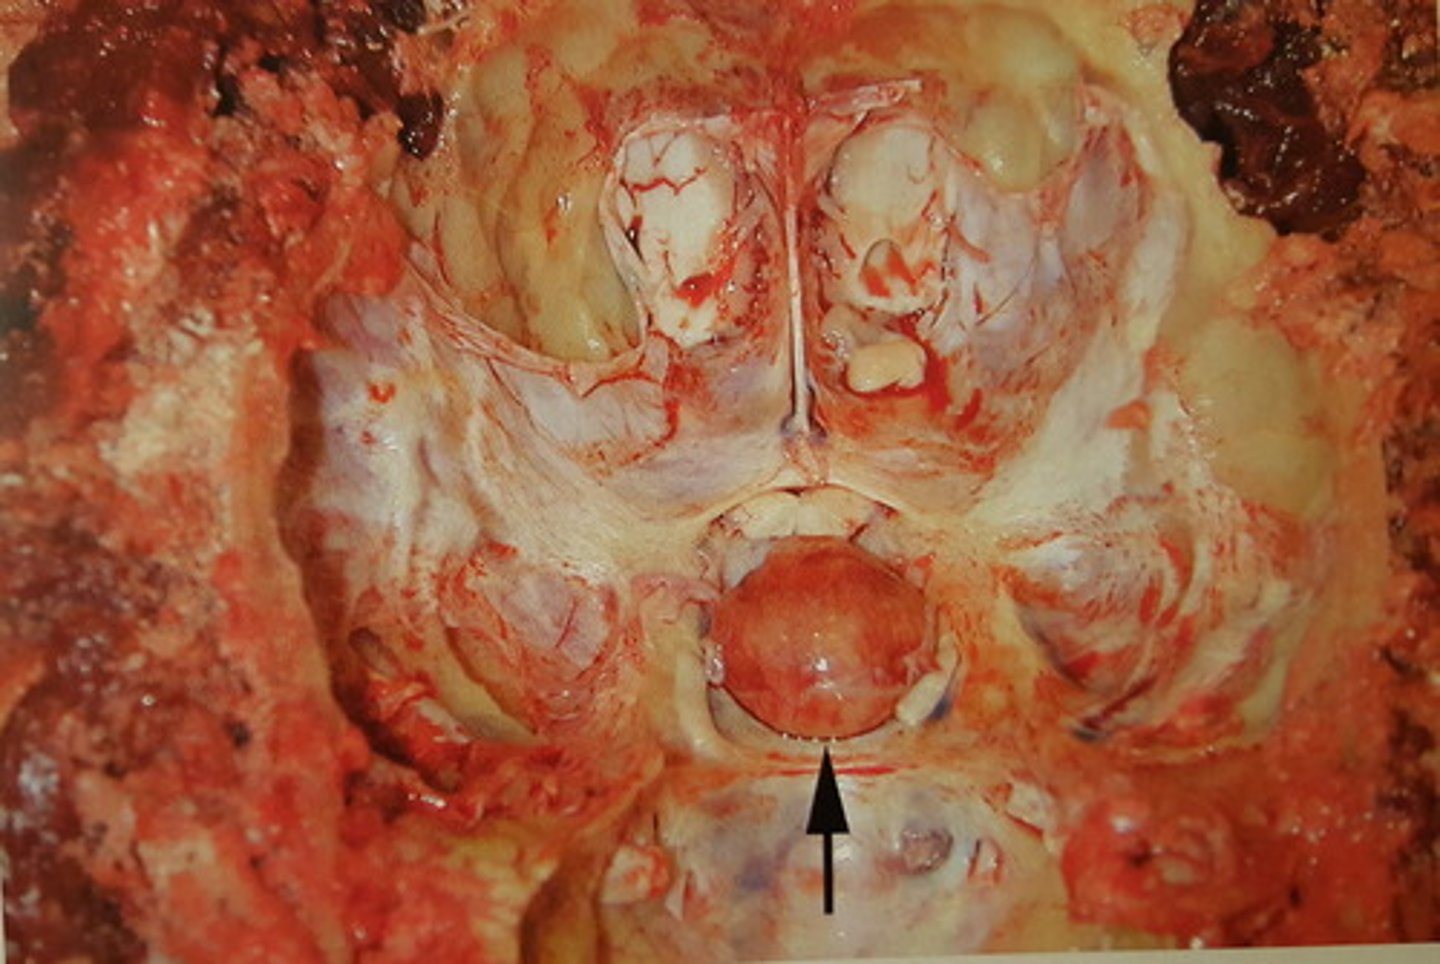

kronisk fokal nekrotiserende meningoencephalitis. hæmatogen

Hjerne fra svin. Patoanatomisk diagnose? patogenesen?

kronisk diffus pyocephali med dilation af ventrikelsystemet

Hjerne fra okse. Patoanatomisk diagnose?

kronisk dissemineret apostematøs encephalitis med abscesdannelse

Hjerne fra okse. Patoanatomisk diagnose?

kronisk dissemineret apostematøs encephalitis. Kan opstå som led i pyæmi

Hjerne fra okse. Patoanatomisk diagnose? Hvordan kan det opstå?

kronisk fokal apostematøs encephalitis. Kan opstå som led i en pyæmi

Mesencephalon hos okse. Patoanatomisk diagnose? Hvordan kan det opstå?

kronisk solitær hjerneabsces. Den kan opstå som led i en pyæmi

Hjerne fra får. Patoanatomisk diagnose? Hvordan kan læsionen opstå?

kronisk, fokal apostematøs osteomyelitis mellem S og O med opbrud til hypofysen. Kronisk meningitis (pil hovede). Purulent encephalitis og pyocephali (pil)

Hoved fra okse. Patoanatomisk diagnose?